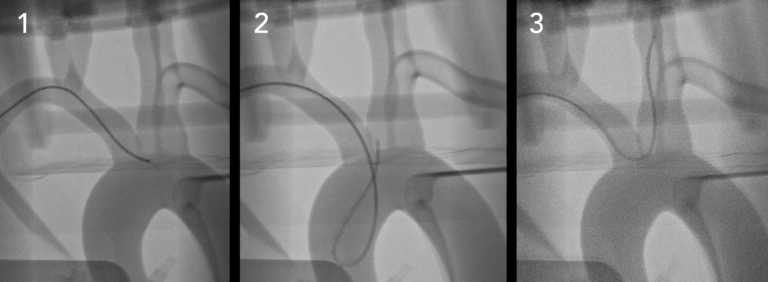

SiM血管造影下的神经径向 轻松模拟各种神经血GJ病状态,例如A脉瘤,中F,AVM等。 在这个平台中,用户可以体验到脉动和真实的触觉反馈。 轻松配置和替换各种特定于患者的模型,以获得一致的结果。 多才多艺 包含: 三、神经血管模拟系统